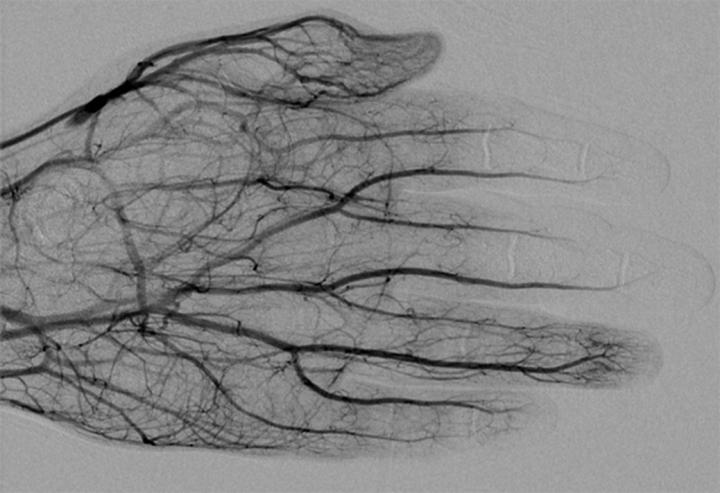

DSA image obtained approximately 24 hours after 1 mg/h IA tPA infusion, 500 U/h heparin via peripheral IV, and daily oral aspirin (81 mg) shows improved perfusion of digital arteries, albeit with suboptimal vascular blush of distal second and third phalanges.